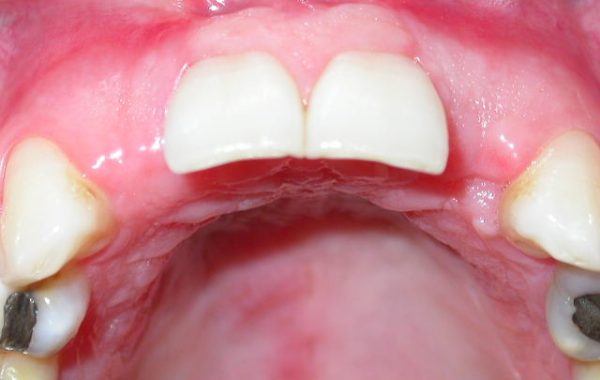

En el siguiente caso se muestran imágenes de una paciente de 35 años de edad, la cual perdió los dientes centrales y laterales del maxilar. La paciente quería una prótesis fija con alta estética. Le mostraremos a continuación la secuencia de este tratamiento.

Paciente que perdió dientes centrales y laterales superiores

Coronas finales colocadas sobre los Implantes Dentales

Foto final de la rehabilitación